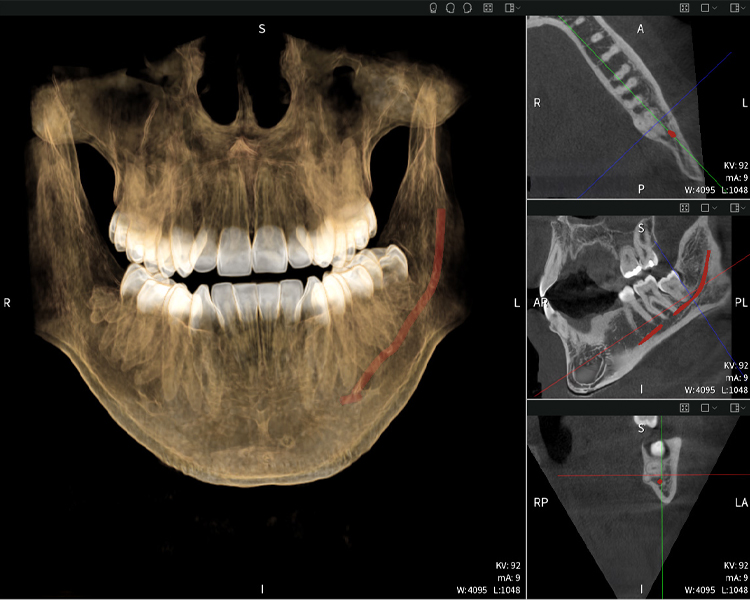

Abbildungen b–d zeigen verschiedene Ansichten einer 3D-Rekonstruktion des Unterkiefers und bieten eine umfassende Übersicht über die Anatomie des Unterkiefers, die Lage der Nerven im Verhältnis zu den Zähnen und ermöglichen die Beurteilung der Zahnsymmetrie und Ausrichtung.

Abbildung d zeigt den bereits vorbehandelten Zahn 48, dessen Krone entfernt wurde und dessen Wurzeln nahe am Nerv belassen wurden, was das hohe Risiko einer Nervenschädigung verdeutlicht.